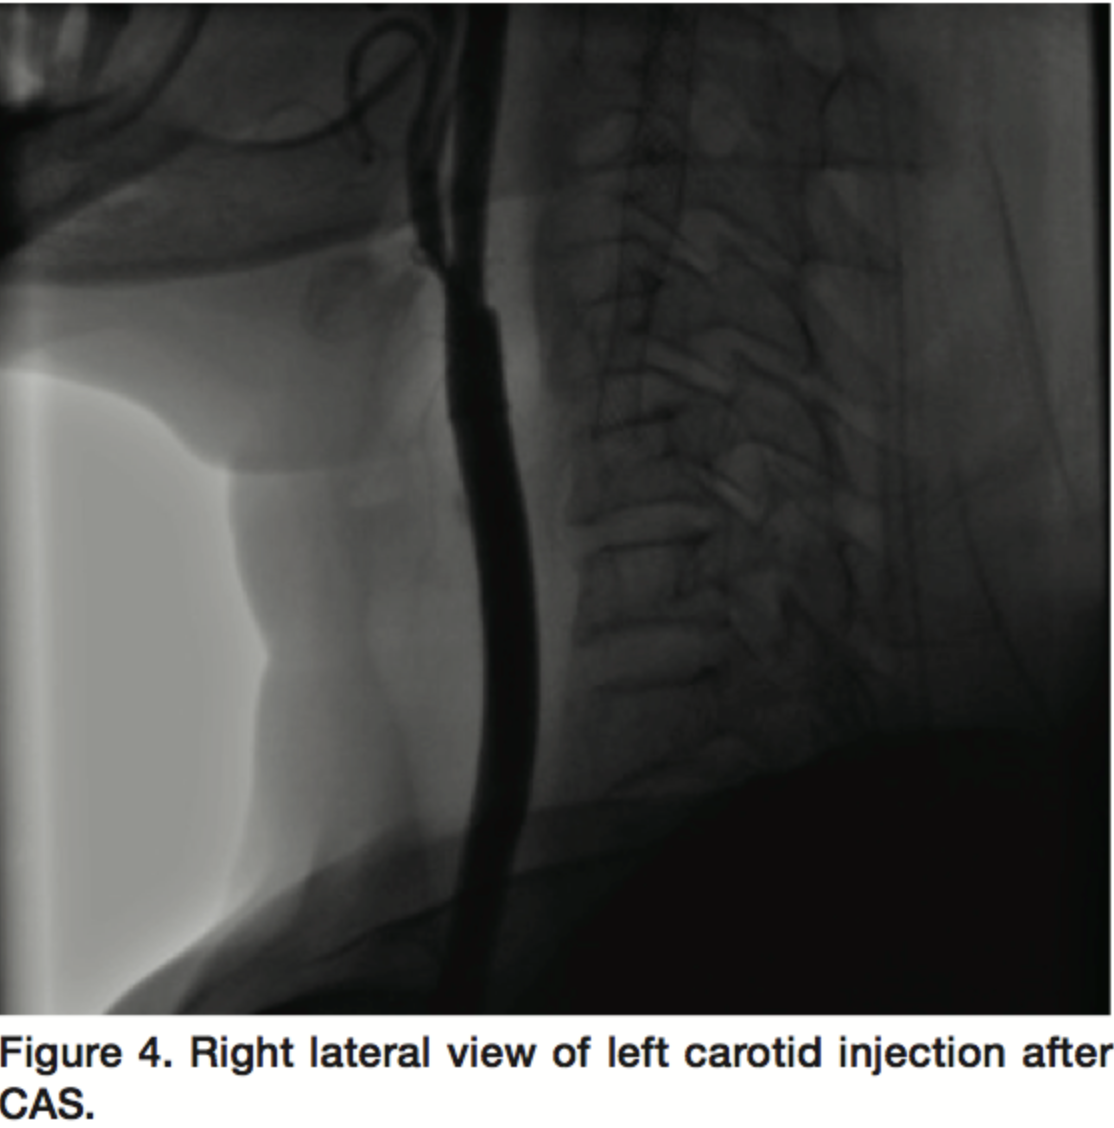

A 64-year-old, hypertensive, diabetic female patient presented with 3-vessel disease and LVEF of 50%. This patient was a good candidate for CABG and had previously undergone carotid artery stenting (CAS) on left internal carotid artery for 95% proximal stenosis. The lesion didn't involve the bulb and wasn't calcified. Her right internal carotid artery also had 85% proximal plaque (Figures 3 and 4). After the procedure, treatment began with normal saline and dopamine to keep blood pressure stable. Dopamine titrated to 15 µg/kg/min but she didn`t tolerate tapering and her blood pressure was dependent on inotrope, which persisted for 4 days. The only abnormality in this case was uncontrolled blood glucose after procedure. Her SBP was 130/80 and FBS was 184 before CAS (Table 2).